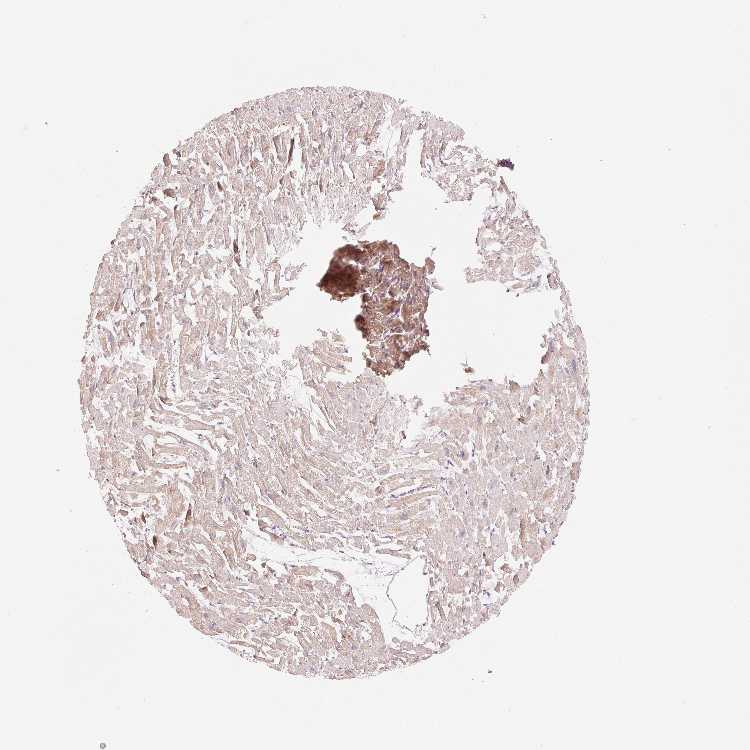

OR13C3